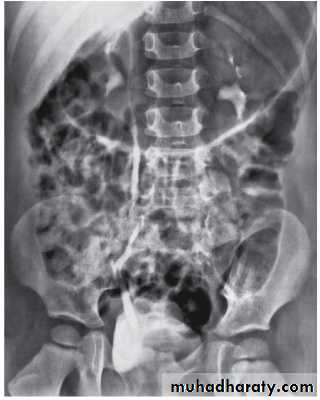

Grading of VUR

The degree of reflux is graded I–V.

Grading is based on the appearance of contrast agent in the collecting system during voiding cystourethrography (VCUG(.

COMPLICATIONS

Hydroureteronephrosis

(1) Increased work load

(2) High hydrostatic pressure

(3) Weak ureteral musculature

The VCUG:

the definitive examination

to diagnose and grade reflux and establish reversible causes

must include a voiding phase:

in some cases, reflux may be seen only during the elevated intravesical pressures associated with micturition.

in visualizing the urethra, may allow the diagnosis of outflow obstruction to be made (e.g., posterior urethral valves).

The intravenous urography (IVU) findings are usually normal in lower grades of reflux.

MCUG